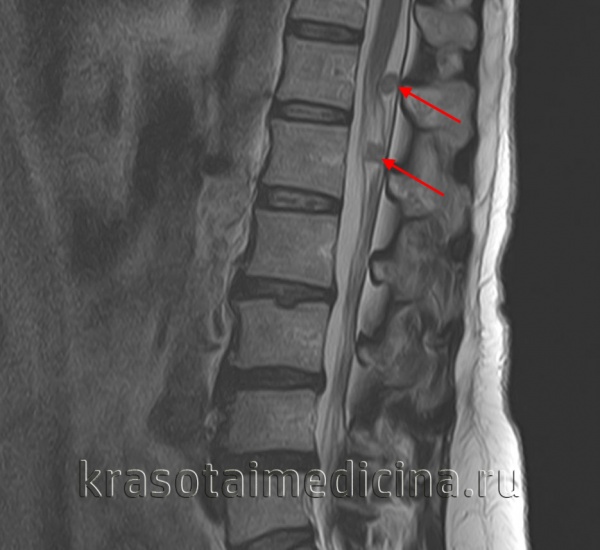

- МРТ. Проводится изолированная МРТ поражённого отдела позвоночника. Исследование позволяет обнаружить невриномы спинномозговых корешков, определить степень спинальной компрессии.